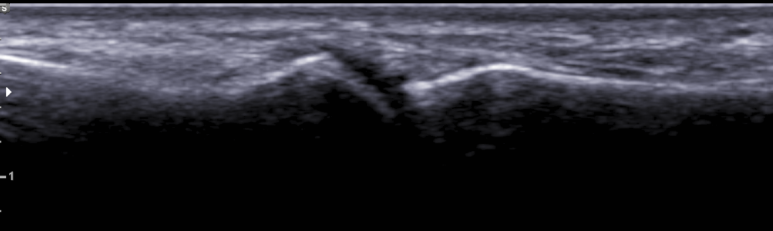

관절의 요산 침착을 보기 위한 1st MTP 관절의 관절초음파; double contour sign (-), tophi (-)